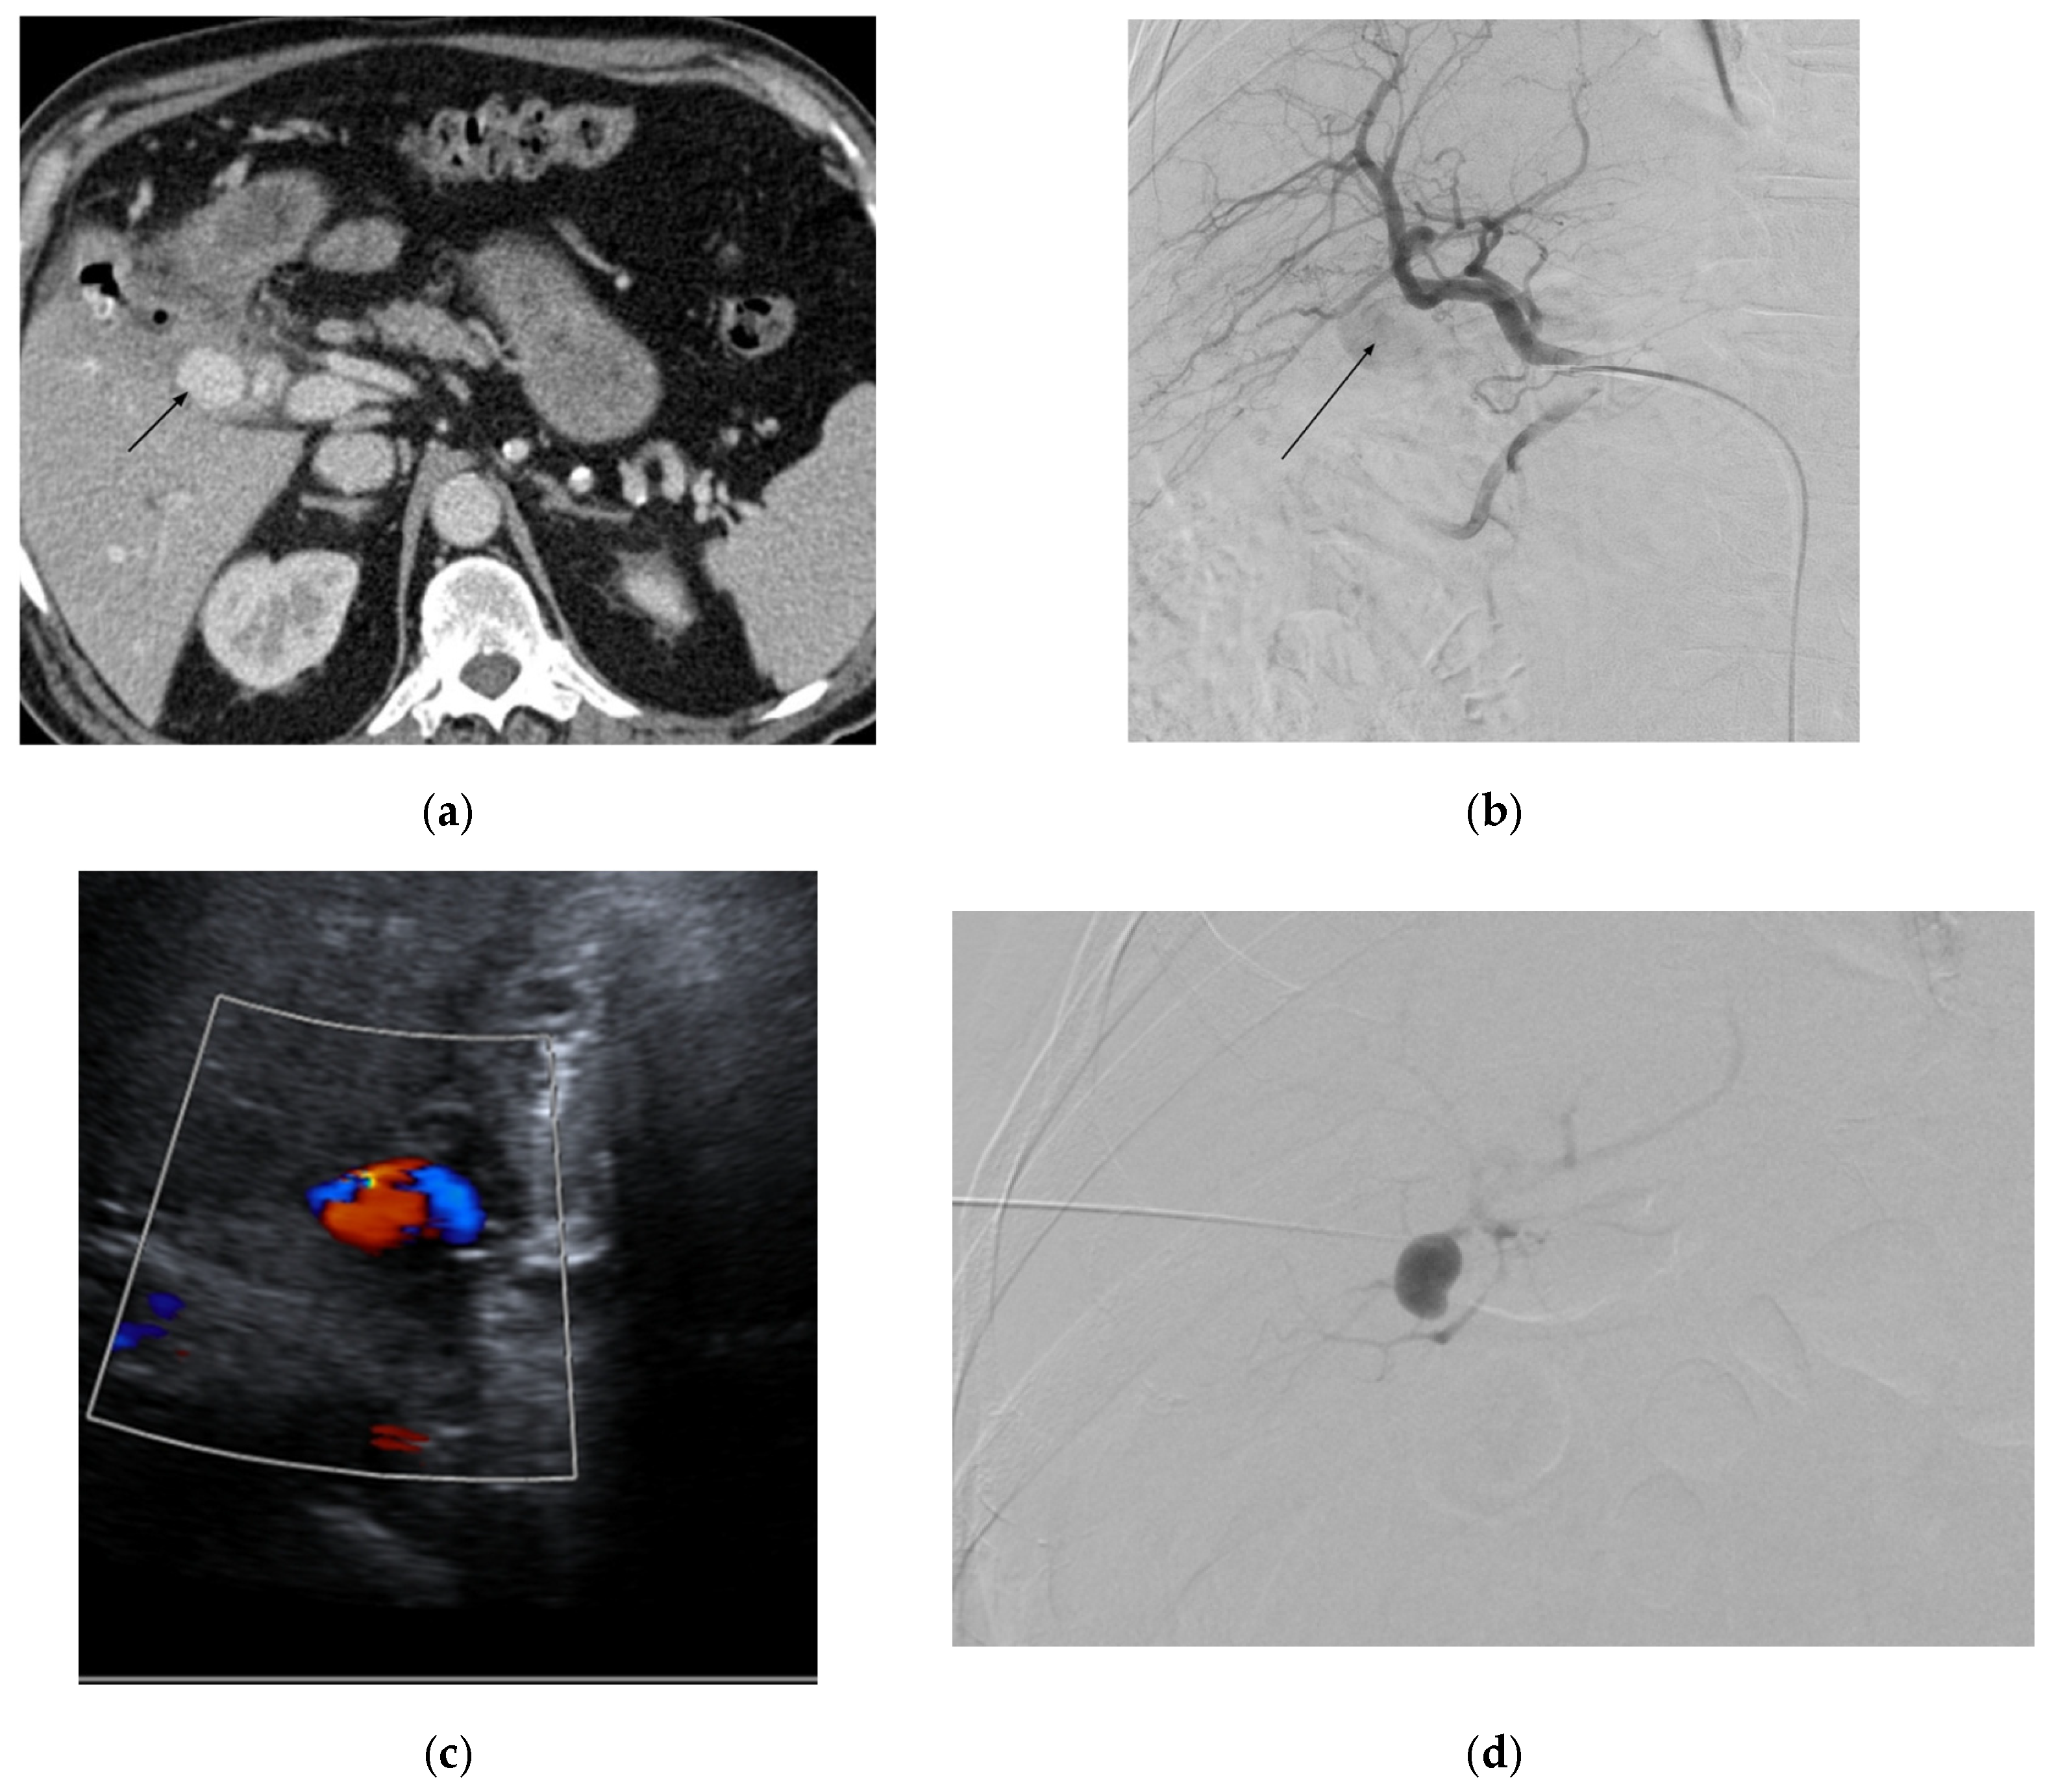

4.2. Left Colic Artery

4.2.4. Diagnosis

4.2.5. Management